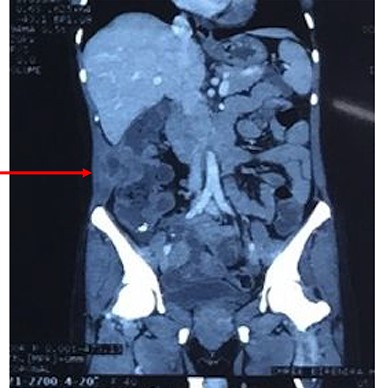

Computed tomography of the abdomen showing perforation of the tumor through muscles of lateral abdominal wall with abscess formation as seen on CT scan.

After resuscitation with intravenous fluids, administration of broad-spectrum intravenous antibiotics and intravenous analgesics, a contrast-enhanced computed tomography (CECT) scan was done to further characterize the lesion. CECT of abdomen showed large abscess extending from the subcutaneous and intermuscular planes over the right iliac fossa and breaching the peritoneum. It showed heterogeneous wall thickening of the proximal part of the ascending colon with loss of mural stratification and causing luminal narrowing, measuring 4.8 × 5.1 × 4.5 cm with surrounding inflammatory changes with adjacent well-defined collection 11.3 × 4.5 × 10.9 cm and few air pockets and infiltrating the right lower abdominal wall (Fig. 2). Pus aspirated from the right abdominal swelling and was sent for culture and sensitivity. Patient was taken up for diagnostic laparoscopy and proceeded.